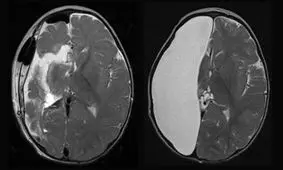

پژوهشگران آمریکایی در بررسی جدید دریافتند عملکرد افرادی که فقط یک نیمکره مغز دارند،کامل است و نقصی ندارد.